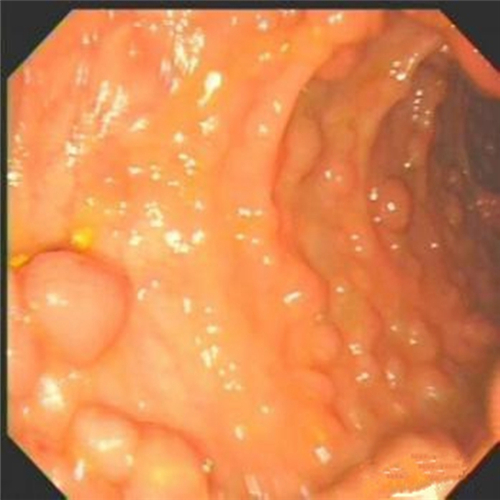

女性直腸息肉

直腸息肉在肛門的

痔瘡與直腸息肉

直腸息肉無蒂

直腸息肉良性